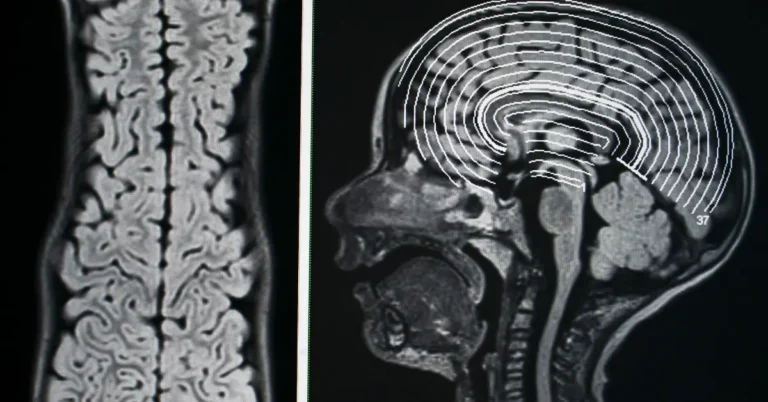

What is Epilepsy? Epilepsy is a chronic neurological condition marked by repeated seizures caused by abnormal electrical activity in the brain. Seizures can range from brief loss of awareness to uncontrollable muscle movements or convulsions. In Ayurveda, this condition is referred to as Apasmara, caused primarily by an imbalance in Vata dosha, with Pitta and Kapha involvement in certain cases.

In Ayurveda, epilepsy is referred to as Apasmara, a Tridoshic disorder predominantly driven by Vata dosha imbalance, often accompanied by Pitta or Kapha disturbances. It is believed to be caused by impaired consciousness due to obstruction in Manovaha srotas (channels of the mind) and dysfunction in Majja dhatu (nervous tissue).